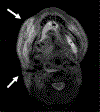

Lymphedema is a devastating disease that has no cure. Management of lymphedema has evolved rapidly over the past two decades with the advent of surgeries that can ameliorate symptoms. MRI has played an increasingly important role in the diagnosis and evaluation of lymphedema, as it provides high spatial resolution of the distribution and severity of soft tissue edema, characterizes diseased lymphatic channels, and assesses secondary effects such as fat hypertrophy. Many different MR techniques have been developed for the evaluation of lymphedema, and the modality can be tailored to suit the needs of a lymphatic clinic. In this review article we provide an overview of lymphedema, current management options, and the current role of MRI in lymphedema diagnosis and management. EVIDENCE LEVEL: 5 TECHNICAL EFFICACY: Stage 5.